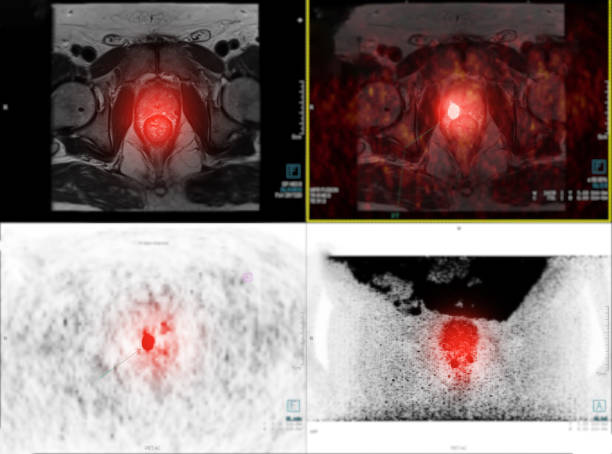

전립선암 초기증상 자세히 알아보기

남성 생식기의 요로계와 직접적 연관이 있는 전립선은 사과 모양으로 배꼽 아래쪽에 위치해 있으며 상당히 중요한 역할을 하고 있습니다. 전립선은 사정을 조절하고, 정자의 움직임을 돕는 전립선 분비액을 만들어냅니다. 이 분비액은 정자의 영양 공급과 이동에 필수적인 성분을 포함하고 있습니다. 또한, 전립선은 방광을 둘러싸고 있는 방광 경화근과 골반 바닥 근육에 대한 지지 구조 역할을 할 수 있어 상당히 중요하나 전립선에도 암이 발병될 수 있어 초기에 원활한 대응을 해야만 합니다. 그럼 이번 시간에는 전립선암 초기증상에 대해 자세히 정리해보겠습니다.

전립선암 초기증상